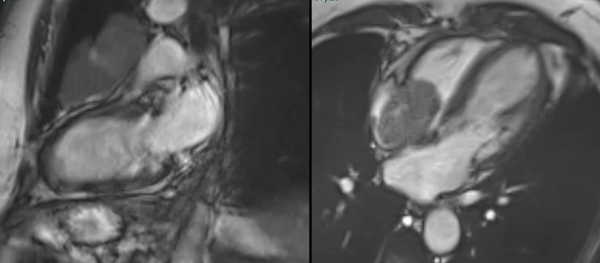

A tumor protocol cardiac MRI often allows a definite diagnosis to be made as in this case.